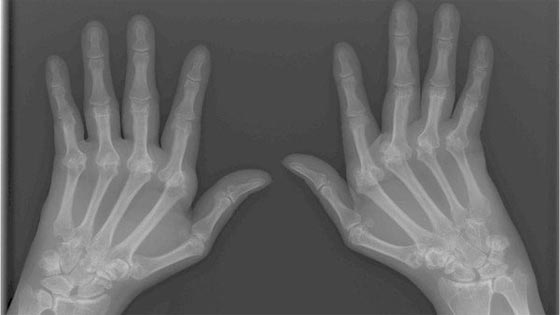

.المرضى المصابون بالتهاب المفاصل يواجهون قلة في المرونة وتورما في المفاصل